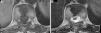

Radiografía lateral de columna dorsal mostrando un aparente aplastamiento vertebral cuneiforme anterior de D10 (A, flecha). La RM mostraba en los cortes sagitales de la secuencia potenciada en T1 un acuñamiento anterior similar al observado en la radiografía (B, flecha), pero en los cortes coronales se evidenció que en realidad correspondía a un defecto de fusión del cuerpo vertebral, que originaba la presencia de 2 hemivértebras, la derecha ligeramente menor que la izquierda, con la apariencia típica de «vértebra en mariposa» (C, cabezas de flechas).